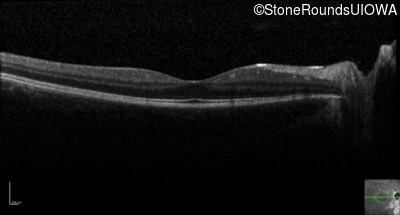

Age at visit: 14 years

Age at visit: 15 years

Age at visit: 16 years

Age at visit: 18 years

Age at visit: 18 years (Visit 2)

Age at visit: 19 years

Age at visit: 20 years

Age at visit: 22 years